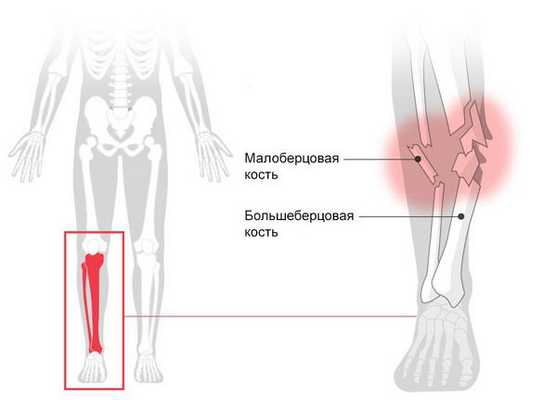

Перелом голени (Fracture of lower leg) — это нарушение целостности большеберцовой или малоберцовой кости. При переломе человек не может опереться на ногу, возникает острая боль, меняется длина и конфигурация голени [1] .

![Перелом голени]()

Диафизарные переломы костей голени. Образуются в результате прямой либо непрямой высокоэнергетической травмы. Возможен перелом только большеберцовой или только малоберцовой кости либо перелом обеих костей голени (самый распространенный). При переломах одной кости смещения отломков не наблюдается, либо оно менее выраженное и проще поддается коррекции, поскольку вторая кость остается целой и удерживает сломанную в относительно правильном положении. Переломы обеих костей - более тяжелые, при них чаще возникает выраженное смещение и чаще требуется хирургическое вмешательство.

Повреждение проявляется болью и выраженным отеком. Наблюдается патологическая подвижность, крепитация. Опора невозможна, движения сильно затруднены. Диагноз подтверждают при помощи рентгенографии. Лечение переломов одной из костей голени чаще консервативное - при необходимости проводят репозицию, затем накладывают гипс. Лечение повреждений обеих костей голени может быть консервативным или оперативным. В первом случае на 4 недели накладывают скелетное вытяжение, а затем осуществляют иммобилизацию гипсовой повязкой. Во втором выполняют очаговый остеосинтез с использованием блокируемых стержней, винтов, реже - пластин, либо внеочаговый остеосинтез с наложением аппарата Илизарова.